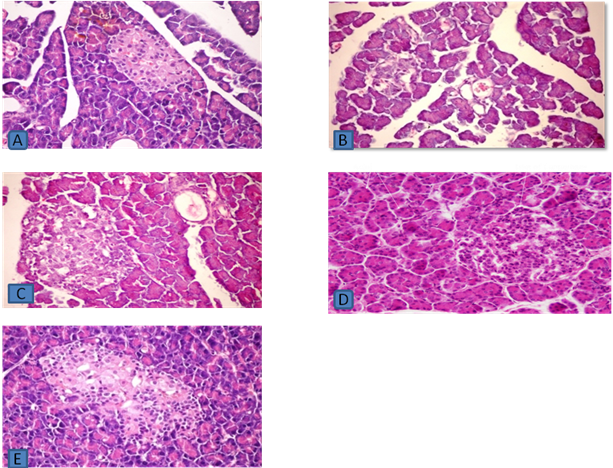

Fig. 1: Pancreas of swiss albino mice stained by haematoxylin (HE) and eosin, A) Pancreas of group-1: Control mice pancreas showing normal architecture and normal distribution of islets cells at 400x, B) Pancreas of group-2: Pancreatectomised mice pancreas showing abnormal architecture, degenerative pancreatic tissue and sign of necrotic islet cells 15 d after the operative procedure at 400x, C) Pancreas of group-3: Pancreatectomised and cyclosporine treated mice showing abnormal architecture, irregular cells, not well defined and necrosis of the cells at 400x, D) Pancreas of group-4: Cyclosporine treated mice displaying normal structure at 400x, E) Pancreas from pancreatectomised mice at the end of the experiment showing improvement or regeneration in morphology of islets of langerhens and restoration of normal cellular population at 400x

The histopathological examination of the pancreas of the control group showed exocrine pancreas and islets of langerhans.

In pancreatectomized group histologically after 15 d of the operative procedure, the sections of the pancreas showed irregular, degenerative, necrotic changes and disturbance in the architecture of acinar cells and reduction in diameter of islets of langerhans as compared to control group. The light micrographs of the pancreas of the pancreatectomized-cyclosporine-treated group showed shrinkage and reduction in diameter of islets of langerhans, also sign of necrotic islet cells as compared to control group.

Cyclosporine treated group showed no significant changes in the cells when compared with the pancreatectomised group. Pancreas from pancreatectomised group at the end of the experimental period showed marked improvement of islets of langerhens and regeneration of β-cells may be due to nesidioblastosis as compared to pancreatectomised group pancreas 15 d after the operative procedure.

The architecture of pancreas (histopathological evaluation) of Pancreatectomised group after 60th d showed regeneration of pancreatic β-cells and a distinct change in the morphological structure as compared to Pancreatectomised animals on d 15th. The biochemical estimation confirmed that there was a restoration of glycaemic status with progress in the number of d and that has been confirmed by the histopathological studies showing probable β-cells proliferation.